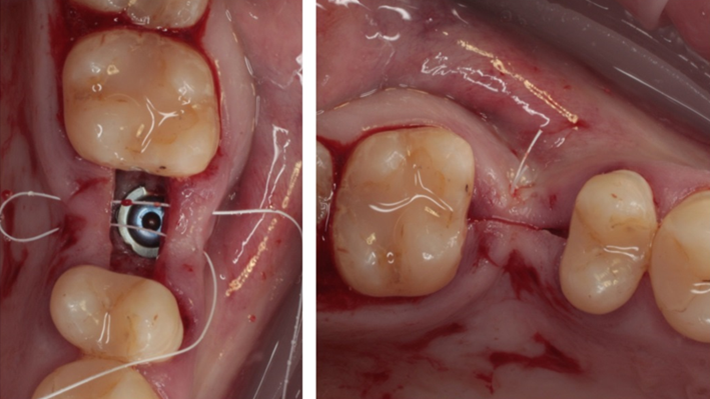

Clinical case: Ridge splitting technique using SmarThor + AnyRidge as expander

- Courtesy of Dr.Kwang-Bum Park, Korea -

Keywords

AnyRidge, ridge splitting, GBR, Dr. Kwang-Bum Park, mandibular posterior, SmartThor, Mega-Oss, thin ridge, bone regeneration

Products:

AnyRidge implant system. SmarThor, Mega-Oss